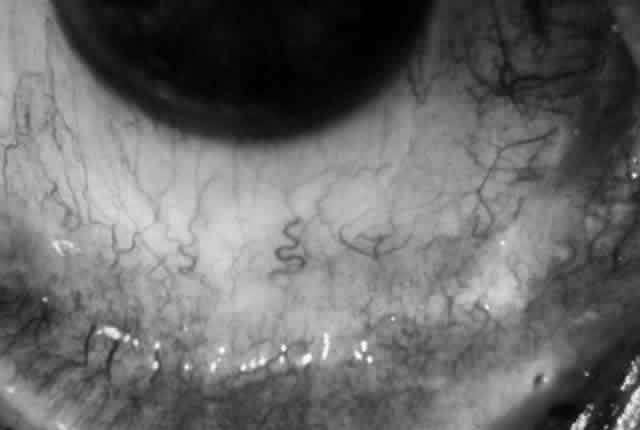

Clinically, the ocular disease in cicatricial pemphigoid (OCP) may present unilaterally in the form of a chronic, recurrent catarrhal conjunctivitis, but it eventually becomes bilateral. Subepithelial fibrosis is characteristic of stage 1 of OCP (Fig. 7). Stage 2 shows fornix foreshortening (Fig. 8), and symblepharon formation is the hallmark of stage 3 (Fig. 9). Stage 4, end-stage disease, is characterized by ankyloblepharon and surface keratinization (Fig. 10). Obstruction of the lacrimal ductules and meibomian gland ducts eventually produces an unstable tear film and progressive sicca syndrome, but it is to be emphasized that OCP is not a dry-eye syndrome until late in the disease course.20 Trichiasis and entropion occur because of the subepithelial fibrosis, with eventual keratopathy, corneal neovascularization, and corneal ulceration and scarring.20

Fig. 7. Stage 1 cicatricial pemphigoid, with cicatrizing conjunctivitis, and fine striae-type areas of subepithelial fibrosis, but without evidence of shrinkage of the conjunctiva.